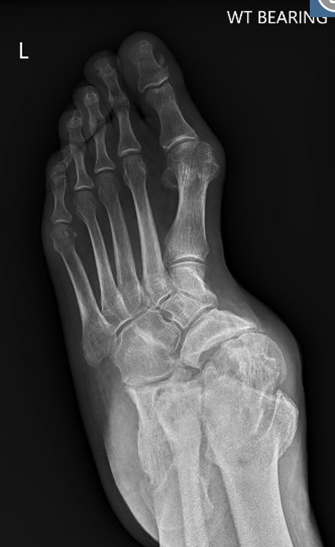

TOTAL ANKLE REPLACEMENT :: ORIF CALCANEUS :: ORIF ANKLE FRACTURE DISLOCATION :: COMPLEX BUNION AND LESSER TOE CORRECTION :: TALUS FRACTURE -1 :: TALUS FRACTURE -2 :: LISFRANC REPAIR :: COMPLEX TRIPLE ARTHRODESIS 1 :: COMPLEX TRIPLE ARTHRODESIS 2 :: MINIMALLY INVASIVE BUNION REPAIR 1 :: MINIMALLY INVASIVE BUNION REPAIR 2 :: ARTHROSCOPIC CARTILAGE REPAIR :: TENEX SPUR DEBRIDEMENT :: Haglunds Debridement and Achilles Repair